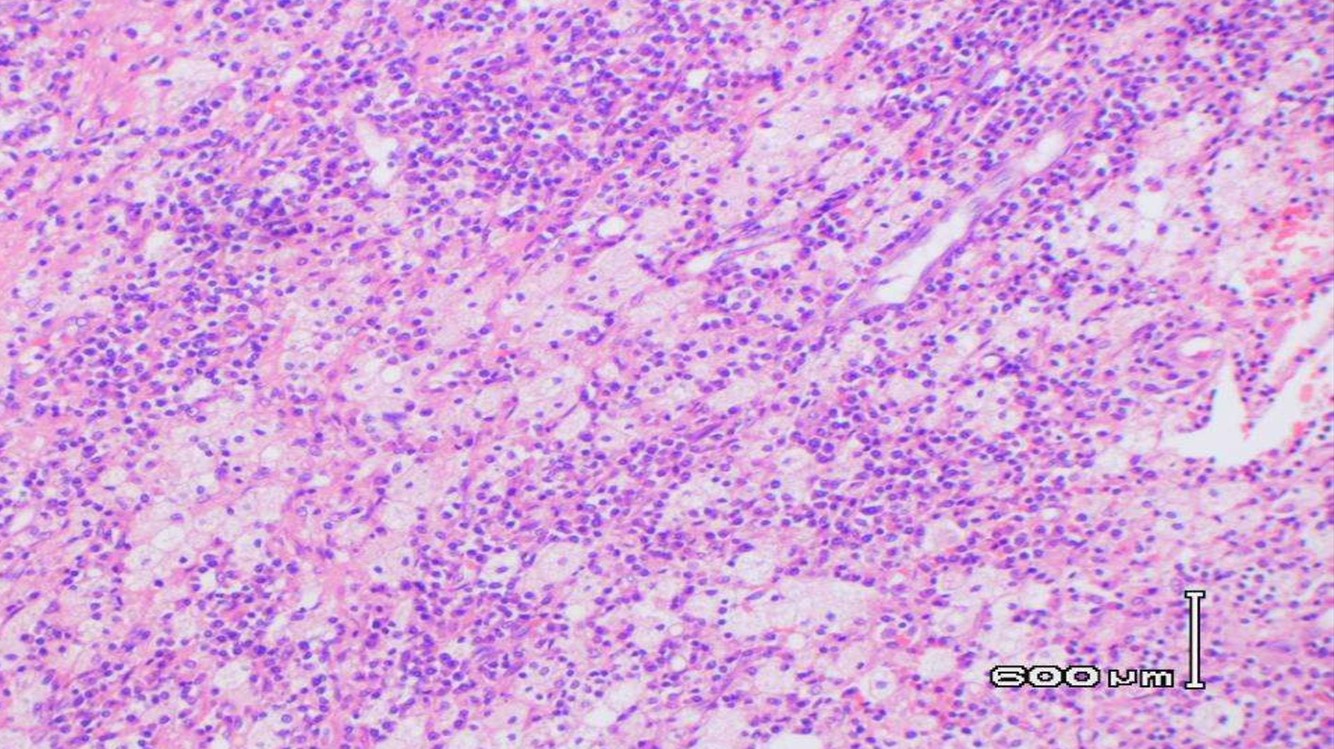

XANTHOGRANULOMATOUS PYELONEPHRITIS

- Often associated with large staghorn calculi of renal pelvis

- Many of these patients may have UTI, secondary to E. coli or Proteus

- May presents as a mass-like lesion